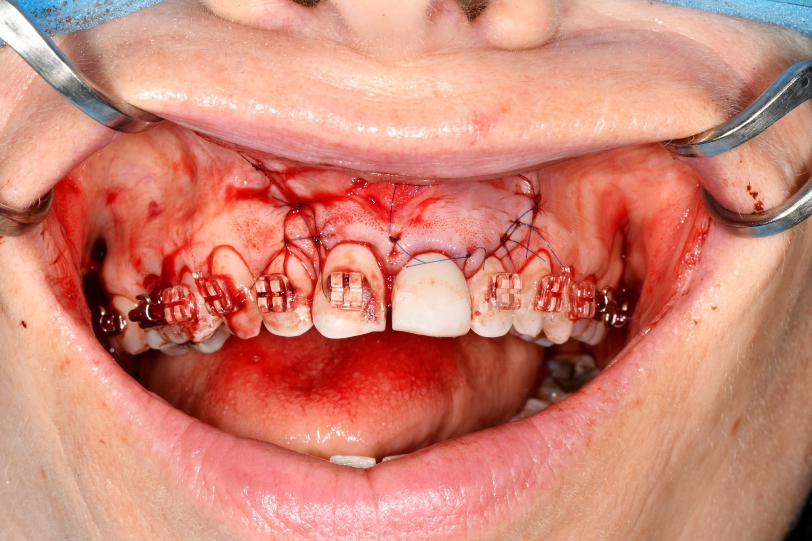

An example of one of the first cases that we did this way is below, including the most recent images of the case.

This illustrates the power of guided surgery and constant improvement.